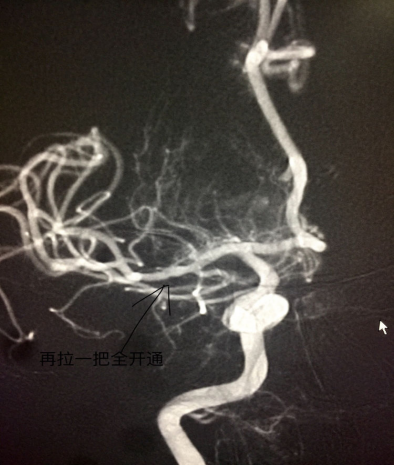

继续拉栓一把后中动脉上干完全开通